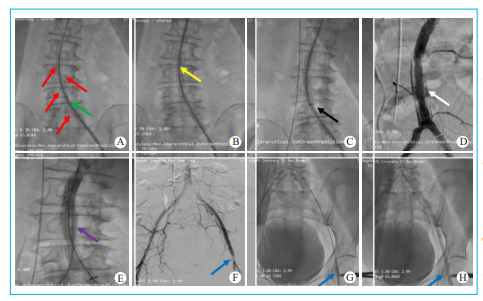

图5 主入路操作困难及并发症的处理 A. 腹主动脉及双髂总动脉弥漫环形钙化(红色箭头)导致20F大鞘扩张器(绿色箭头)预扩时无法推入腹主动脉;B. 更换为18F大鞘扩张器(黄色箭头)预扩时可推入腹主动脉;C. 20F大鞘(黑色箭头)无法推入腹主动脉而采用无鞘技术完成经导管主动脉瓣置换;D. 经导管主动脉瓣置换术毕腹主动脉造影显示腹主动脉环形夹层(白色箭头);E. 腹主动脉覆膜支架植入及球囊后扩张后造影显示腹主动脉夹层消失;F. 左侧股总动脉穿刺点夹层导致局限性狭窄;G. 经右侧股动脉翻山路径行左侧股总动脉球囊扩张压迫左侧股总动脉穿刺点;H. 最终造影显示左侧股总动脉狭窄解除并且血流通畅。

采用20F戈尔鞘管的扩张器,沿着超硬Lunderquist导丝进行预扩张,然后将20F戈尔鞘管沿着超硬Lunderquist导丝尝试送入(图5)。

大鞘预扩张技术